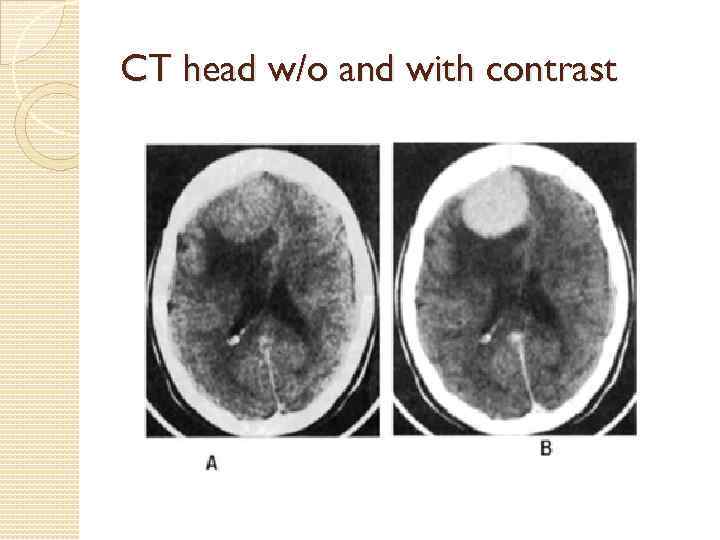

CT head w/o and with contrast

CT imaging: non-contrast or contrast” However, noncontrast CT may not identify brain abscess, herpes simplex encephalitis, and lymphoma and toxoplasmosis in HIV+ patients Clinical presentation would guide ordering of contrast-enhanced CT